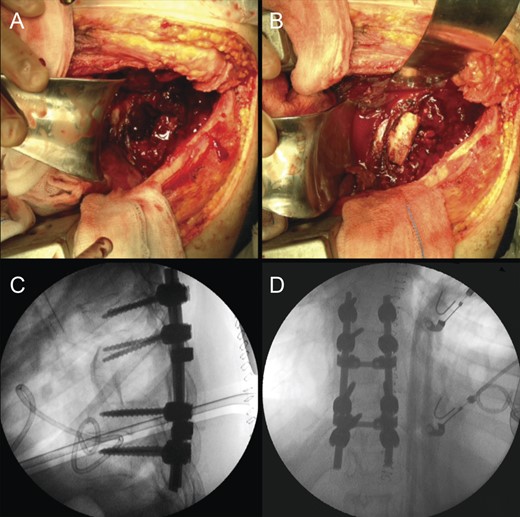

Due to the advanced stage of the lesion, with associated instability that could result in major neurologic deficits in a short time period, a total en bloc spondylectomy of T8 by a posterior-only approach was performed (Fig. 2). The operation followed the technique proposed by Tomita et al. and was complemented with anterior-column reconstruction with a titanium mesh filled with structural allograft, as well as pedicle screw instrumentation, from T6 to T10 (Fig. 3). During the procedure, the eighth dorsal nerve routes were sacrificed.

Intraoperative photographs; after total en bloc spondylectomy (A), anterior-column reconstruction was accomplished with placement of a titanium cage with structural allograft (B) and was complemented with pedicle screw-rod fixation (C). (D) Resected vertebra.

Due to the ongoing postoperative infection, a new operation was undertaken with surgical debridement of the infected tissues, allograft and titanium mesh extraction, which were replaced by iliac crest tricortical autograft for anterior support (Fig. 6). The posterior pedicle instrumentation was kept, after copious irrigation of the surgical wound. Drains were placed in the thoracic cavity and paravertebral spaces.

Revision procedure; a thoracotomy was performed for pus drainage and debridement, as well as removal of the anterior cage and allograft (A). A tricortical iliac bone autograft was used to maintain anterior-column stability (B). Postoperative radiographic study (C and D).